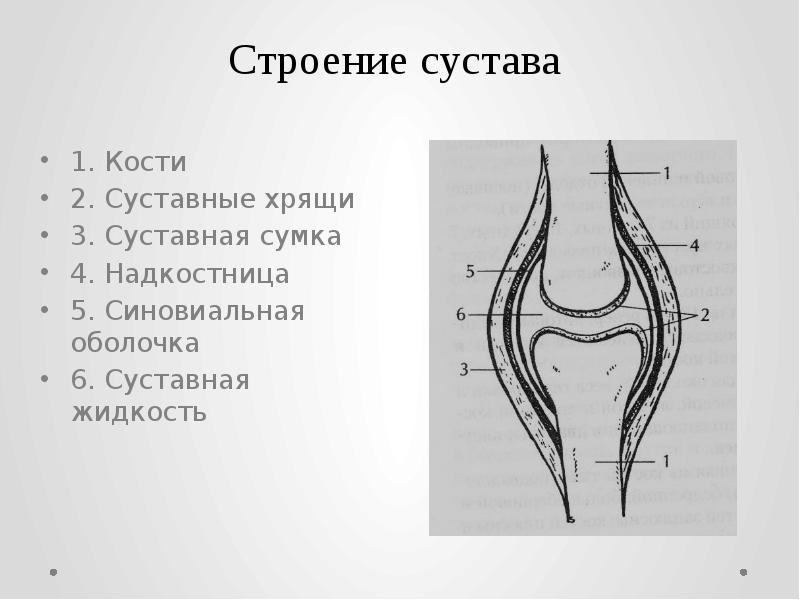

Суставная Жидкость и Головка Сустава: Обзор и Здоровье